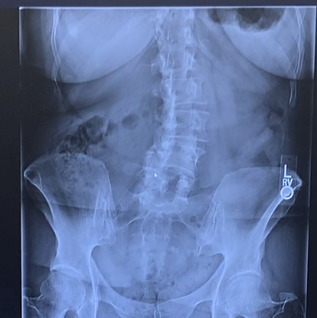

Jane Maldonado

Hello my name is Jane Maldonado. I had both hips replaced by an HSS hip and knee surgeon and would like to thank him for giving me another opportunity at my life. I arrived in his office feeling devastated and in a lot of pain - almost unable to walk. I thought that my life was over because I could no longer do the things I wanted to do. Now I am back to do what I like to do in life and I feel great! I had my first surgery around Father's Day, and I was very surprised when my surgeon visited me at the Hospital on Father’s Day with his son. He showed me that he was truly interested in me as a human being by checking on me during his special day. To me, he is the best doctor and I am blessed that he did my surgery. My surgeon is caring, respectful and passionate about helping people that have trouble walking due to knees and hips problems. I feel like a new person and I am looking forward to life with my new hips. The people that work with him in the office and at the hospital cared for me with love which gave strength to get better. His office staff is professional at all times and make me feel as I am part of the family. I am very thankful to my surgeon and his staff for all they have done for me!